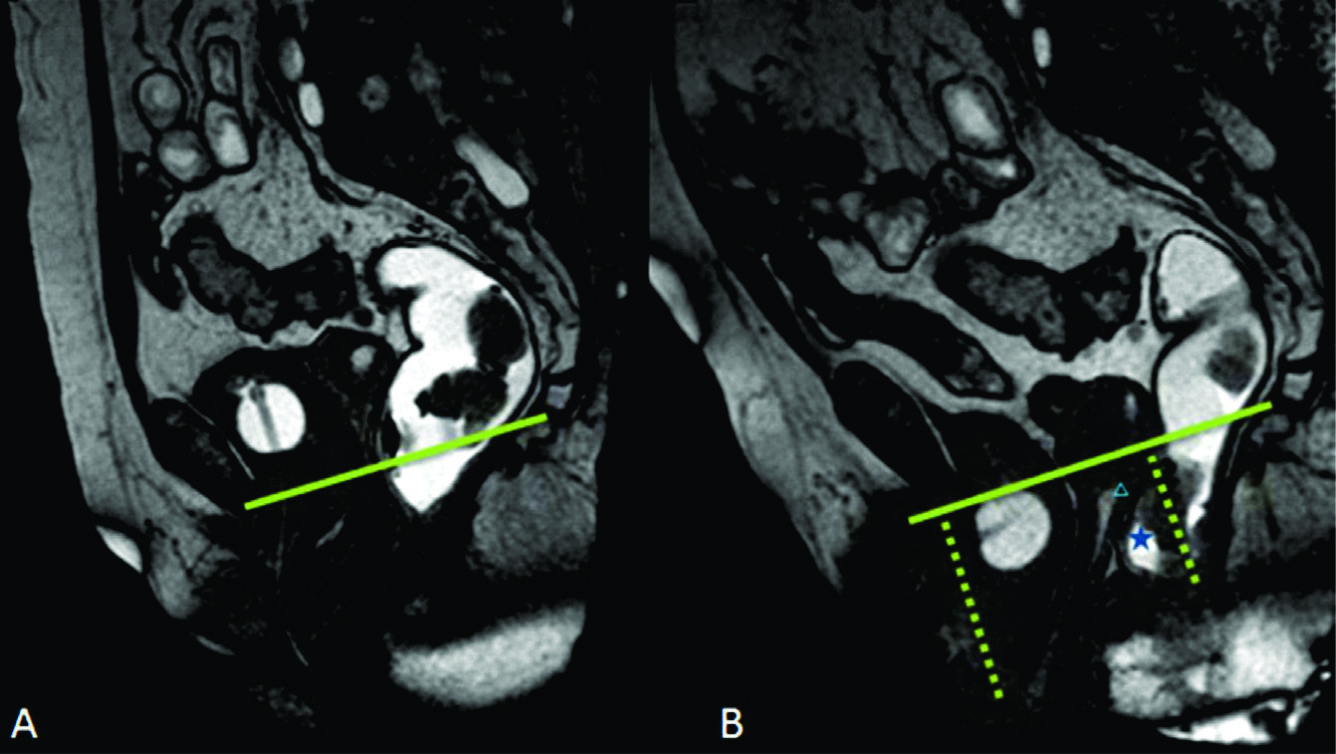

Figura 4

Línea H y línea M.Imágenes potenciadas en T2 de alta resolución en el plano sagital. Se observa el cambio en el valor que adopta la línea M y la línea H al comparar el reposo frente a la defecación. Según sus medidas en centímetros, se puede graduar en cuatro estadios diferentes.

La línea H se traza desde el borde inferior del pubis hasta la pared posterior del recto a la altura de la unión ano rectal, representando el diámetro anteroposterior del hiato urogenital, con un valor normal menor a 6 cm (Ver figuras 4).

La línea M es perpendicular a la PCL a nivel del sector más posterior de la línea H y representa el descenso del hiato del elevador, con un valor normal menor a 2 cm. El ángulo ano rectal es el ángulo entre el eje central del canal anal y la pared posterior del recto, con un valor normal entre 108º y 127º y una variación de hasta 15º en Valsalva.

Además se debe valorar la relajación del piso pélvico, a través del valor que adquiere tanto la línea H (apertura del hiato urogenital) como la línea M (descenso del piso pélvico) durante las maniobras dinámicas (Ver tabla 4) (7).